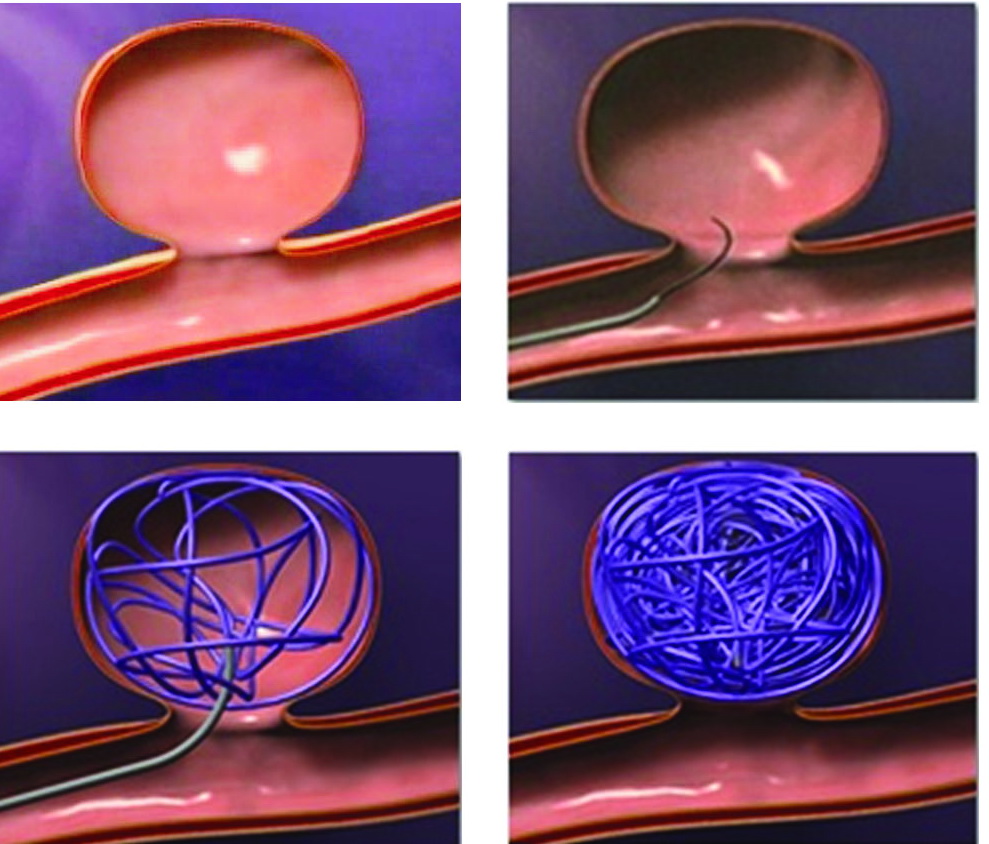

Снимки и иллюстрации микроаневризм сосудов головного мозга